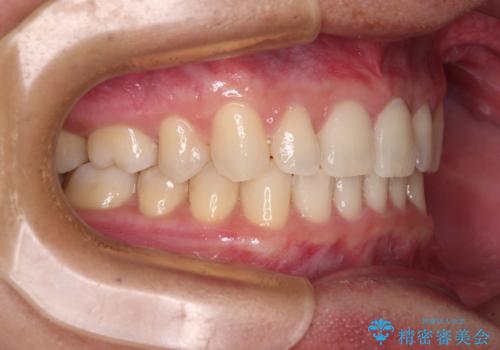

著しいディープバイトと隙間だらけの歯列

- 歯のデコボコと歯の隙間を気にして来院された患者様です。

隙間の原因は、埋伏や前後に重なってしまっている上顎小臼歯と、下の前歯が見えなくなるくらいのディープバイトで、それらを改善する必要がありました。